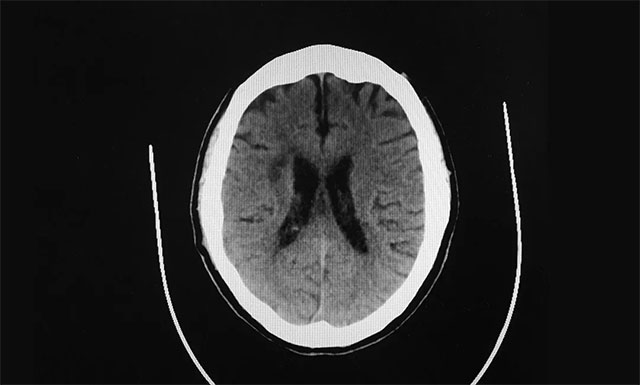

▲ 患者多发性脑梗,致使双下肢活动障碍

“在该医院老伴进行了头部CT检查,医生告诉我们他为多发性脑梗,听到‘脑梗’两字,当时心里咯噔了一下,因为身边有许多老人突发脑梗,之后大多都长期偏瘫在床,恢复好得很少,加之老伴还身患多种疾病,真怕他以后只能在轮椅和床上度过了”,每想到这里,妻子管女士有些不知所措。

“王先生患有多发性脑梗,颅内血管多处狭窄,临床表现为双下肢肢体功能障碍。尤其是左下肢无力比较严重,当时入院时左下肢肢体肌力仅为2+级,而其右下肢肢体肌力也只有3级,不能独自站立与行走”, 周君主任介绍道。